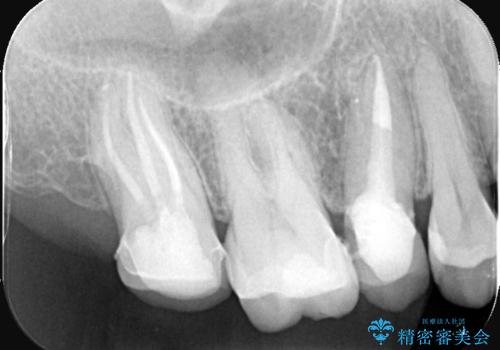

セラミッククラウンによる奥歯の修復

担当医 河口智英